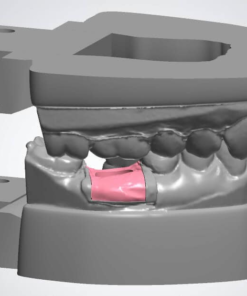

All on X Implant Bridge – CAD Design

Digitally designed All on X implant bridges by Viet Dental Lab. Restore full arches with CAD precision, esthetics, and long-term function on 4–6 implants.

All on X Implant Bridge - CAD Design